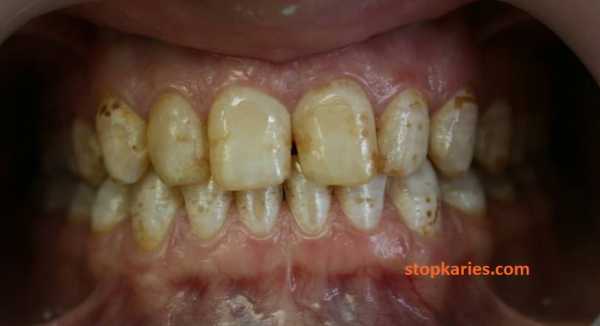

- И на последок, небольшой клинический случай. К стоматологу могут прийти с этим.

У данного пациента множественный кариес, пародонтит, переодонтит нескольких зубов, хронические пульпиты, патология прикуса, повышенная стираемость зубов, клиновидные дефекты. Не правильно расположенные нижние зубы мудрости.

Данная ситуация — довольно распространенный в практике случай.